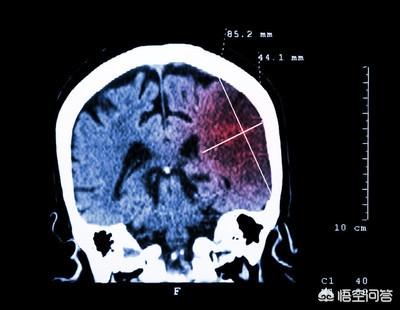

脳梗塞。虚血性脳卒中は、主に中高年に発症する一般的な脳血管疾患で、臨床的には「虚血性脳卒中」として知られている。

脳梗塞は非常に一般的であり、主に脳組織の虚血と低酸素性壊死が起こり、脳梗塞を引き起こす。最も一般的な原因は動脈硬化である。

脳梗塞は、脳の動脈が閉塞して血管が詰まることで神経が障害され発症するもので、突然発症することが多く、人々の油断を誘う。実際、脳梗塞についてあまり知らない人も多く、脳梗塞の発症は前兆がないことばかりではない。

脳血管障害で血栓が生じたら要注意 まず、血管の弾力性が徐々に失われ、徐々に硬くなることがあります。また、余分な脂質などが血管壁に付着して血管が狭くなることもあります。脳梗塞の患者さんの多くは、発症初期に頭痛、ろれつが回らない、眠いなどの副作用を頻繁に経験します。血管が詰まる場合、生活習慣が関係していることが多い。